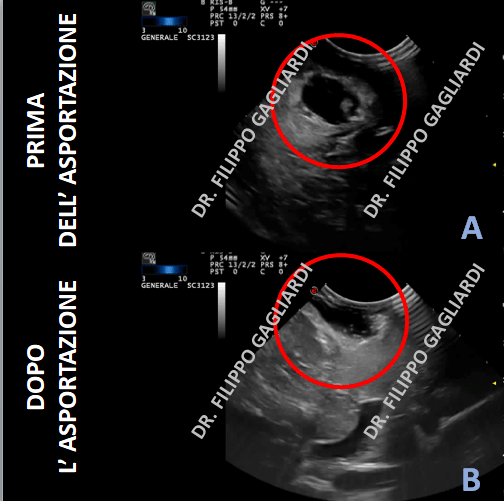

Patologia gliale

Resezione gliomi ad alto grado